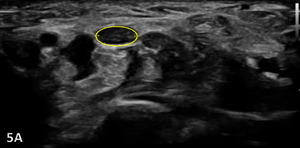

Normal Sonographic Appearance

The median nerve is clearly identifiable in SAX by a well circumscribed ovoid structure with hypoechoic fascicles in a honeycomb-like pattern deep to the roof of the carpal tunnel, the flexor retinaculum, and more superficial to the flexor digitorum superficialis and flexor digitorum profundus tendons. The median nerve is also very compressible and will alter its shape depending on the volume of the anatomical spaces with which it courses. The median nerve cross-sectional area (CSA) can be measured in four sites: 1) the proximal border of the pronator quadratus muscle, 2) proximal to the carpal tunnel inlet, 3) at the tunnel inlet, and 4) at the tunnel outlet.9

Pathological Findings in Median Nerve Pathology at Wrist

A maximal CSA of 12 mm2 or greater at any location is typically diagnostic for CTS.6 More recent evidence shows that CSA may vary based on subgroupings including age, sex, ethnicity, geographical location, and method of CSA assessment.10 An increase in size greater than 2 mm comparing proximal (at pronator quadratus) to distal (at wrist crease) can diagnose carpal tunnel syndrome with 99% accuracy.11

Carpal Tunnel Syndrome can be identified by the following images:

Hypoechoic thickening due to swelling and edema

Disruption of fibrillar pattern

Associated joint effusion